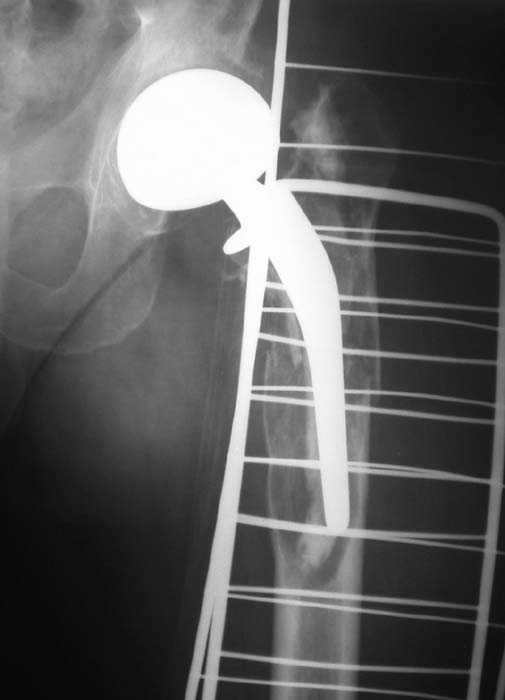

Мужчина, 39 лет.По поводу двустороннего асептического некроза головок бедренных костей последовательно выполнено тотальное эндопроезирование левого (1998 г), затем правого (1999 г) тазобедренных суставов.

26/06/06

Нет никакого смысла делать операцию в два этапа. С чашкой все понятно - стандартный подход с установкой пресс-фит компонента. На бедре имеет

место перипротезный перелом В3 типа - т.е. перелом вокруг ножки с ее нестабильностью на фоне выраженного остеолиза. Решение - доступ к каналу

через перелом с удалением самой ножки, костного цемента и рубцовых тканей. Установка ножки дистальной фиксации (типа Solution), длину ножки

надо определить по шаблону. Минимальный контакт ножки с интактной костью - 6-8 см. Фрагменты проксмального отдела собираются на ножке

эндопротеза, дефекты костной ткани заполняются чипсами (аллографт) и фиксируются кортикальными аллографтами, уложенными дополнительно по типу

"вязанки хвороста" серкляжом. Мы имеем 8 или 10 подобных наблюдений и результатами довольны.